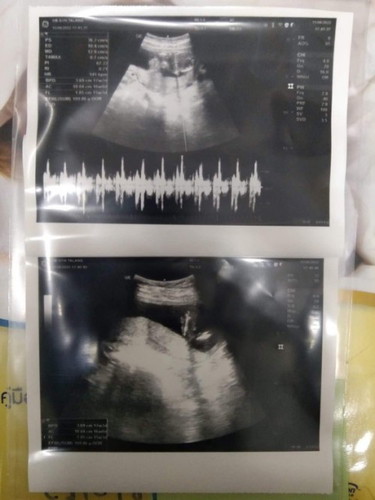

16w3d ลุงหมอบอก70%เป็น ญ

คุณพ่อดีใจเลย หมอบอก70%เป็น หญิง แต่ก็ลุ้นเดือนหน้าให้ชัวค่ะ